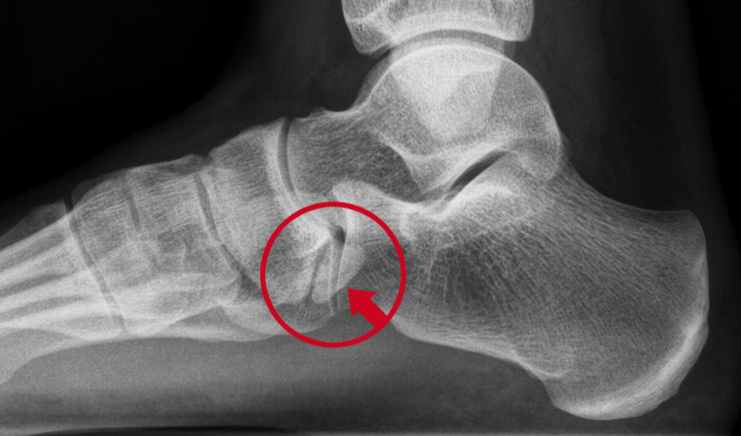

Os trigonum

Röntgenfoto van een os trigonum.

Het os trigonum geeft vaak klachten bij dansers en atleten. Het botje veroorzaakt irritatie (inklemming) van de weke delen aan de achterzijde van de voet, als de tenen helemaal naar beneden wijzen. Denk maar eens aan het dansen op spitzen.